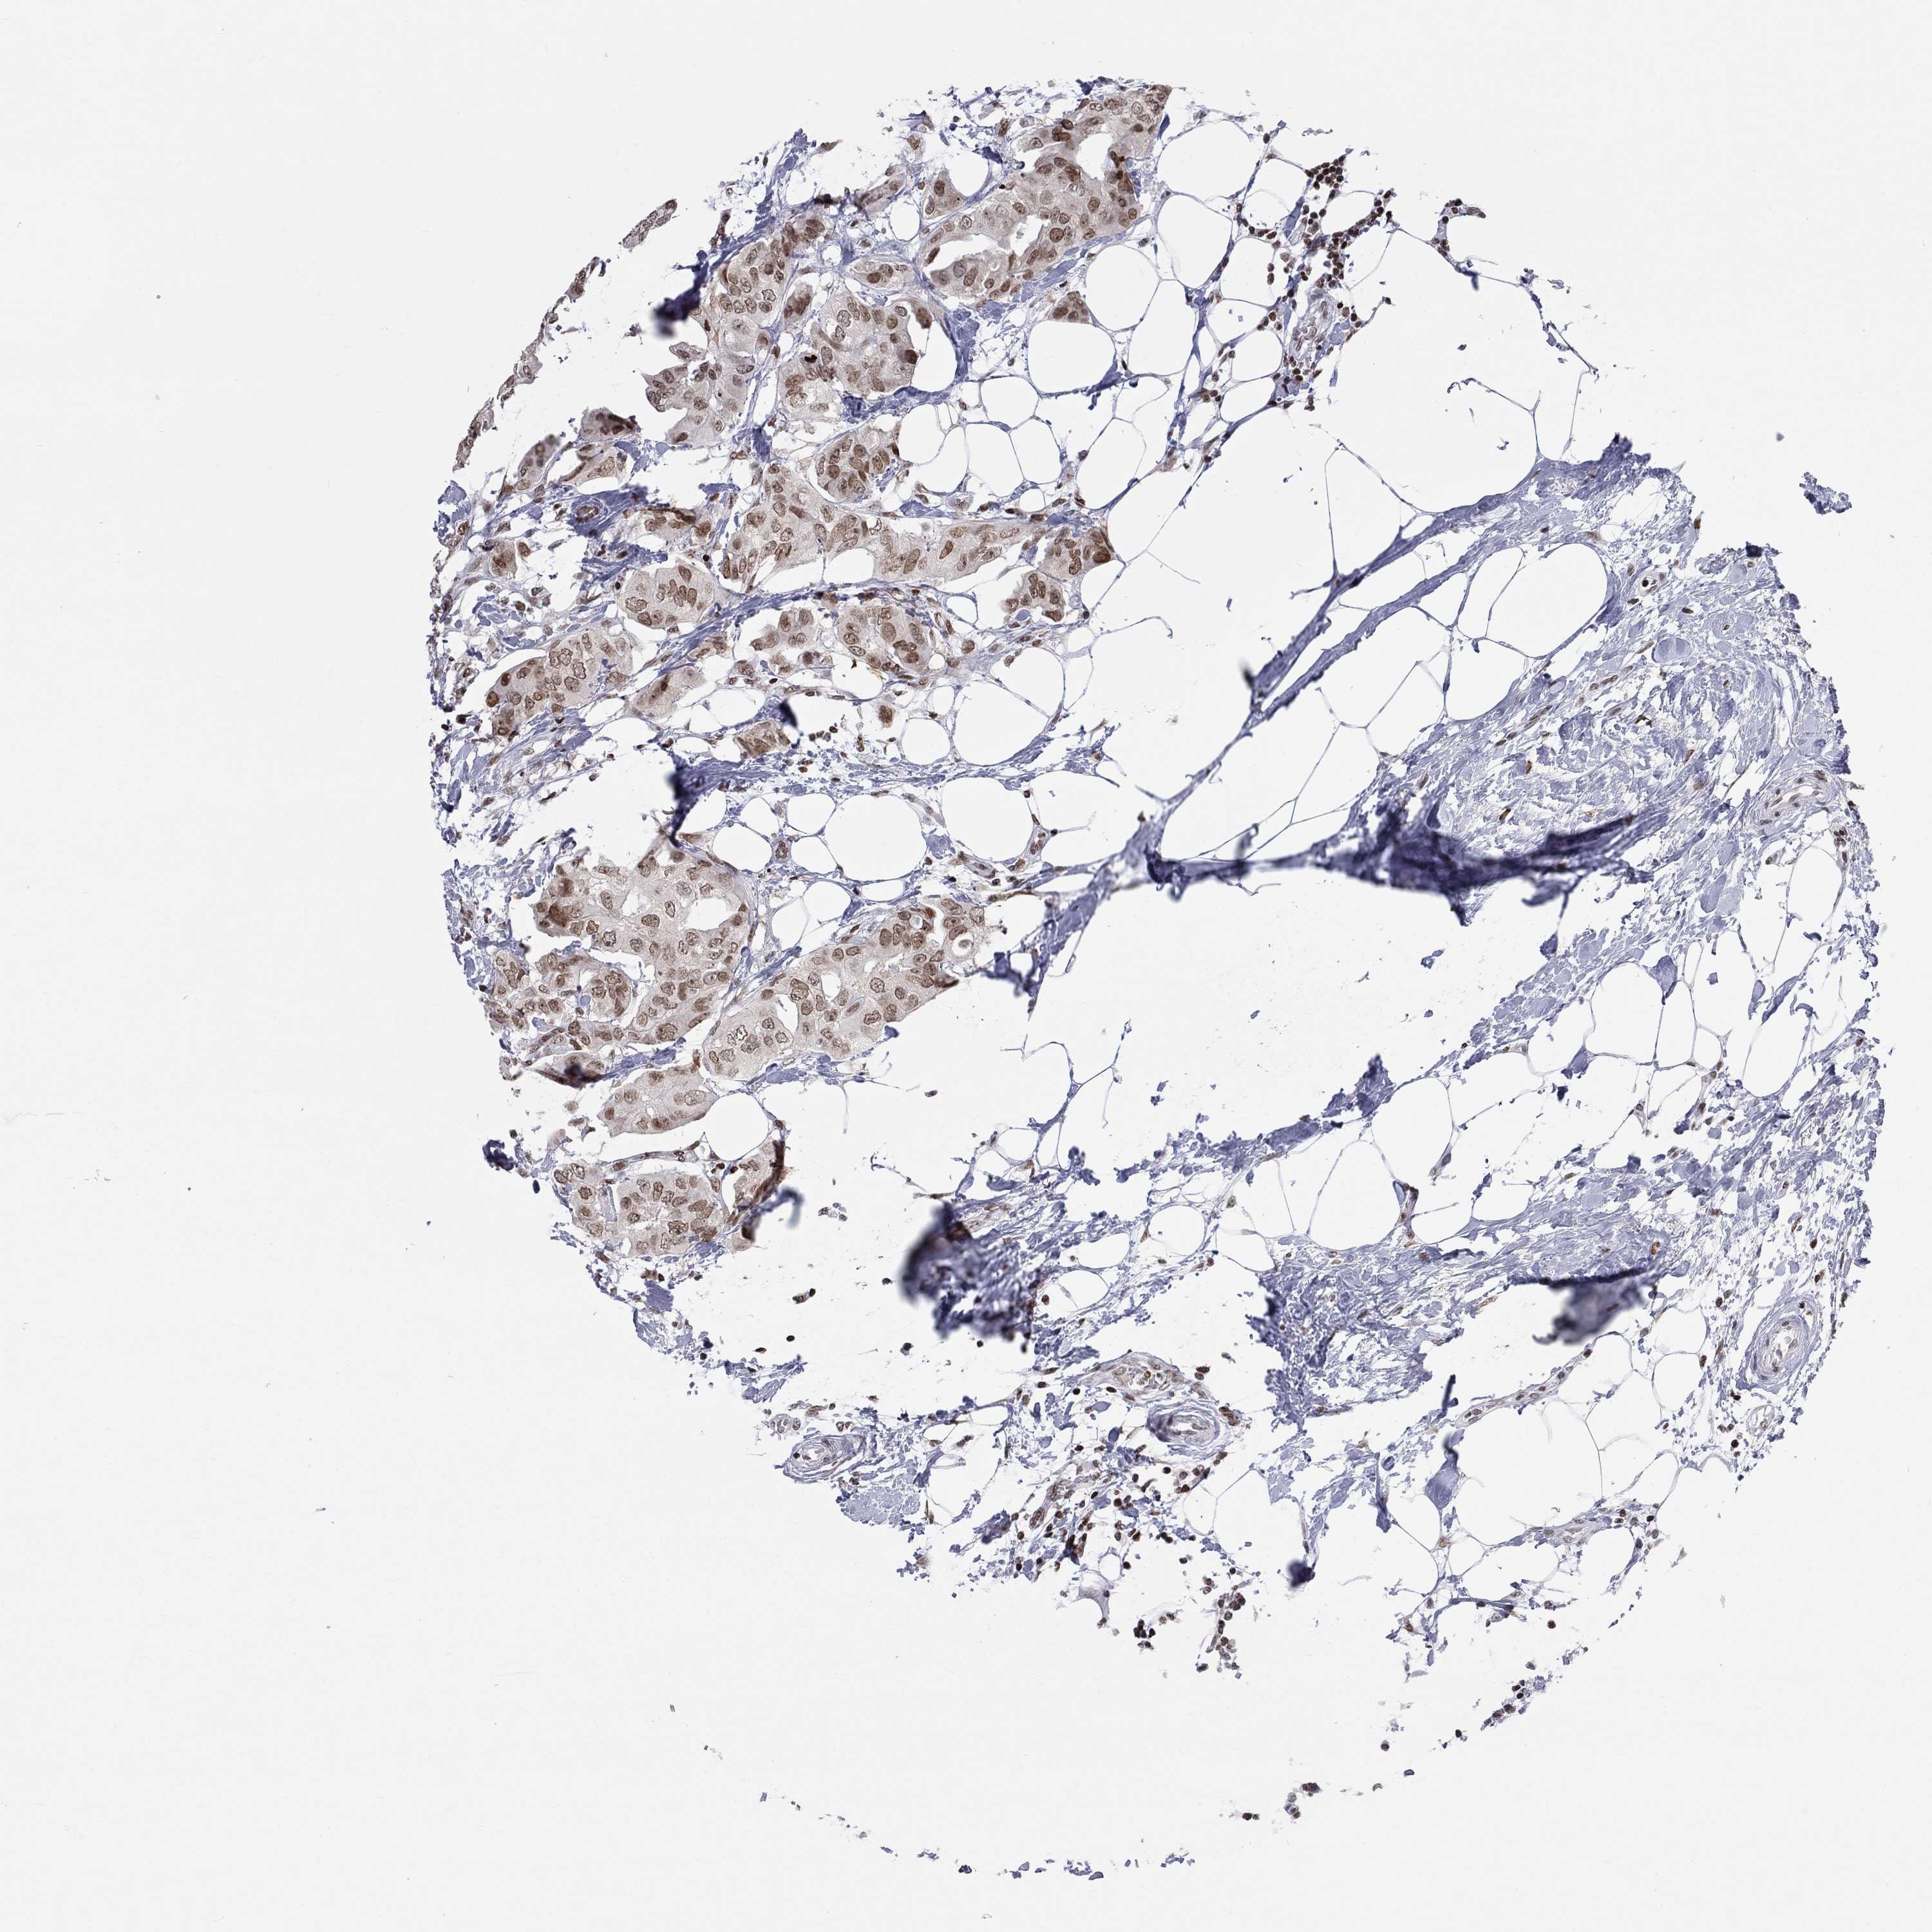

CANCER BREAST CANCER Show tissue menu

BRCA TCGA BRCA VALIDATION PROTEIN EXPRESSION